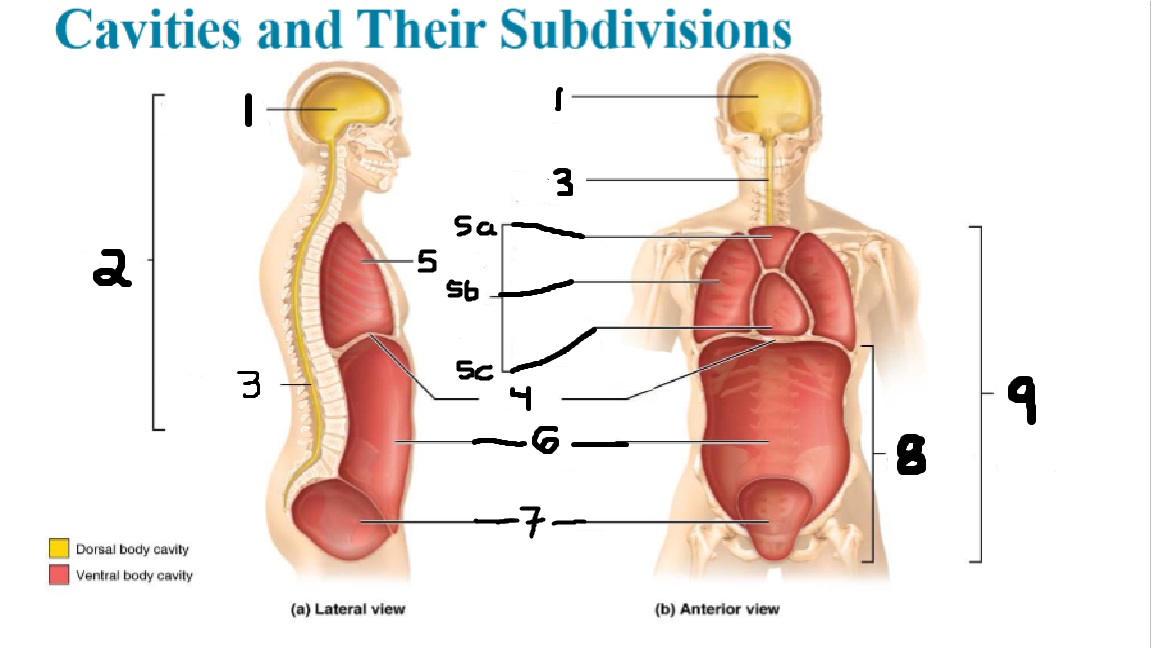

What cavities are part of the dorsal cavity?

The cranial and the Spinal (vertebral) cavities

What kind of cavity is labeled 2?

The dorsal body cavity (containing the cranial and spinal cavities)

What is the purpose of the dorsal cavity?

protects the nervous system

What is the main organ encased by the cranial cavity?

the brain

What cavity is labeled #1?

The cranial cavity

What is the main organ encased by the vertebral cavity?

the spinal cord

What is another word for the vertebral cavity?

the spinal cavity, or the spinal canal

What body cavity is labeled 3?

the vertebral cavity.

What cavities are included in the ventral cavity?

the thoracic, abdominal, and pelvic cavities.

What body cavity is labeled #6?

the abdominal cavity.

What are the main organs of the abdominal cavity?

the digestive organs such as the stomach, intestines, spleen and liver

What cavities are included in the Abdominopelvic cavity?

the abdominal cavity and the pelvic cavity

What body cavity is labeled #8?

The Abdominopelvic cavity

What does the diaphragm separate?

the thoracic and the abdominal cavities

What is labeled #4?

the diaphragm

What organs does the pelvic body cavity contain?

urinary/reproductive organs and rectum

What is labeled #7?

the pelvic cavity

What does the thoracic cavity encase?

the heart and the lungs

What is labeled #5?

the thoracic cavity

What part of the thoracic body cavity is labeled 5a?

superior mediastinum

What part of the thoracic body cavity is labeled 5b?

pleural cavity

What part of the thoracic body cavity is labeled 5c?

pericardial cavity within the mediastinum

What body cavity encloses the heart?

the pericardial cavity.